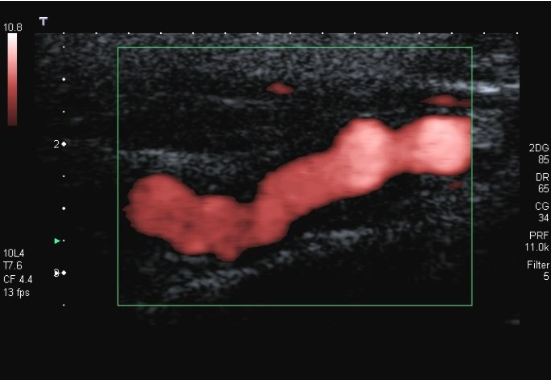

Patient presents to ultrasound department for preoperative work-up. Patient scheduled to have coronary artery bypass graft (CABG) in two days. Patient has HX of peripheral vascular disease, smoking, HTN and hyperlipidemia. You obtain this image. Consider following questions.

1. Is it possible to have plaque producing stenosis without symptoms?

2. What are the risk factors for atherosclerosis in this patient presentation?

3. Is this image diagnostic for hemodynamically significant stenosis? Why or why not.

Yes

Hx of peripheral vascular disease, smoking, HTN, hyperlipidemia. (Also has CAD because they are here for pre op for CABG)

No because power doppler only shows presence of flow and no velocity information